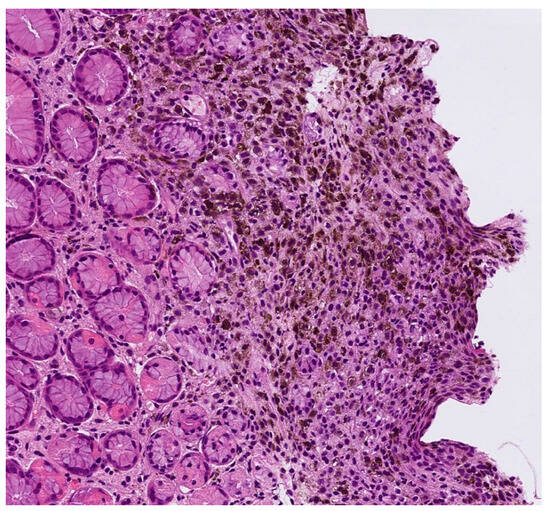

| Case | Age in Years/Gender | Clinical Morphology | Dermoscopic Features | Histology |

|---|---|---|---|---|

| 1 | 53/M | Blue–black plaque with multiple bluish papules and macules | Homogenous blue–gray pattern with yellow hue | Locally advanced melanoma |

| 2 | 86/M | Blue–black plaque with multiple blue satellitosis | Homogenous blue–gray pattern | Metastatic melanoma |

| 3 | 38/F | Blue nodule with agminated pigmentated macules | Homogenous violet-blue pattern with serpentine vessels | Desmoplastic blue nevus |

| 4 | 77/F | Blue–black macule and interspersed pigmentated lesions of scalp | Homogenous blue–brown pattern | Common blue nevus |